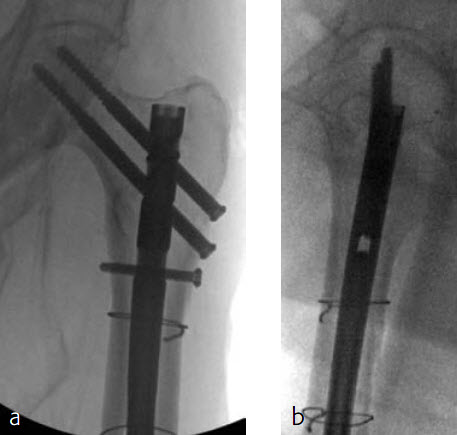

Case 1: Subtrochanteric femur fracture

An 86-year-old patient fell at home while dressing, sustaining a subtrochanteric left femur fracture (Fig 1). The CT scan confirmed no involvement of the intertrochanteric region or the piriformis fossa. Fixation was with FRN for piriformis fossa entry point in reconstruction locking mode and transverse locking (Fig 2).